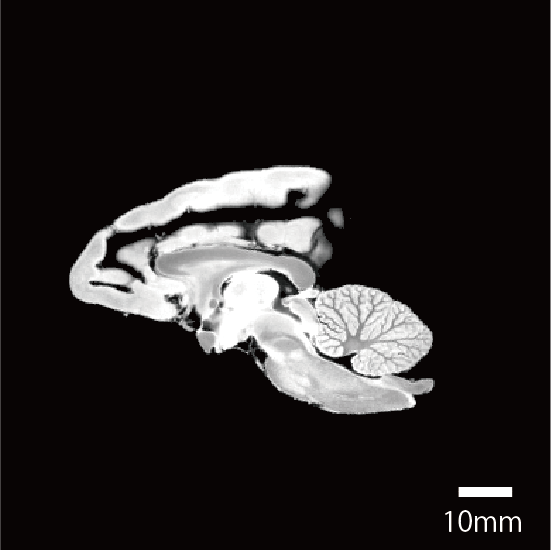

撮像情報

| T2強調画像 | 拡散テンソル画像 | |

| エコー時間 (TE) (秒) | 7.5 | 20 |

| 繰り返し時間 (RT) (秒) | 600 | 650 |

| 励起回数 (NEX) | 3 | 1 |

| 有効視野 (FOV) (mm) | 84, 67.2, 50.4 | 84, 67.2, 50.4 |

| マトリクスサイズ | 320, 256, 192 | 160, 128, 96 |

| 空間分解能 (µm) | 0.21 | 0.53 |

| b0 | - | 2 |

| 撮像時間 | 6時間 43分 | 53時間 14分 |

脳標本画像

| 拡散強調画像 |

![]() |